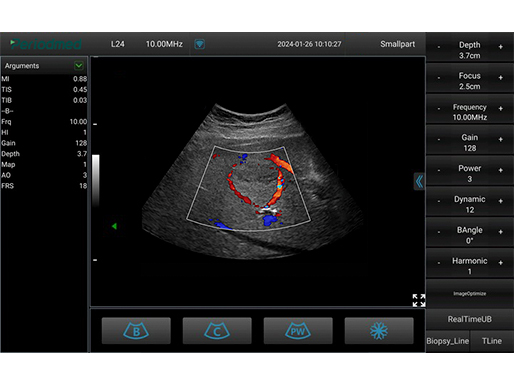

彩色模式 甲状腺

彩色模式 甲状腺

彩色模式 甲状腺